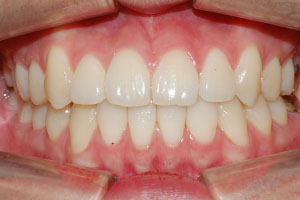

치료증례 전후사진

Before & After